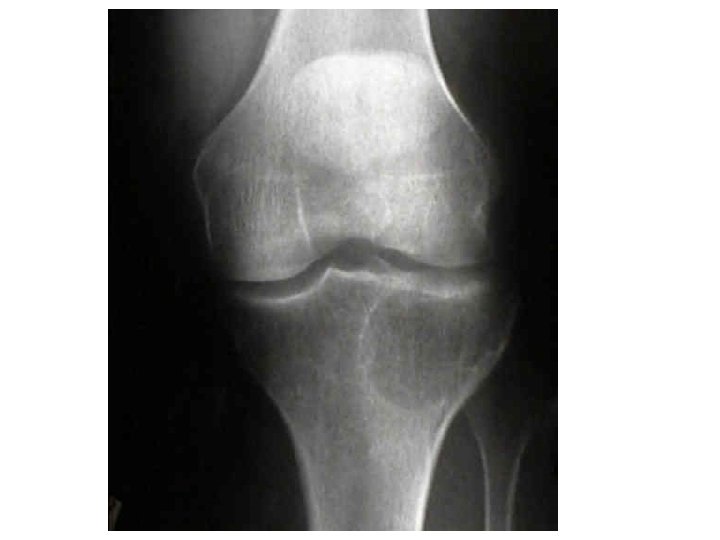

Gout • Gout is a disease that results from an overload of uric acid in the body. This overload of uric acid leads to the formation of tiny crystals of urate that deposit in tissues of the body, especially the joints. When crystals form in the joints it causes recurring attacks of joint inflammation (arthritis). Chronic gout can also lead to deposits of hard lumps of uric acid in and around the joints and may cause joint destruction, decreased kidney function, and kidney stones.